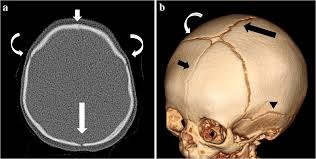

4. الأشعة المقطعية ثلاثية الأبعاد

الأشعة المقطعية ثلاثية الأبعاد (3D CT Reconstruction) تُعد أداة حيوية لتشخيص حالات التحام عظام الجمجمة المبكر (Craniosynostosis). فهي توفر رؤية دقيقة للجمجمة وبنية العظام، مما يسمح للطبيب بتقييم أي التصاقات غير طبيعية بين الصفائح العظمية، وتحديد نوع التحام العظام وشدته بدقة متناهية. تساعد هذه التقنية أيضًا في تخطيط العلاج أو الجراحة بشكل آمن، حيث يمكن تصميم التدخل الجراحي أو خوذة تصحيحية وفق شكل الجمجمة الفعلي، مما يزيد من فعالية العلاج ويقلل المخاطر المحتملة، ويضمن متابعة نمو الرأس بطريقة دقيقة خلال الأشهر الأولى من عمر الطفل.